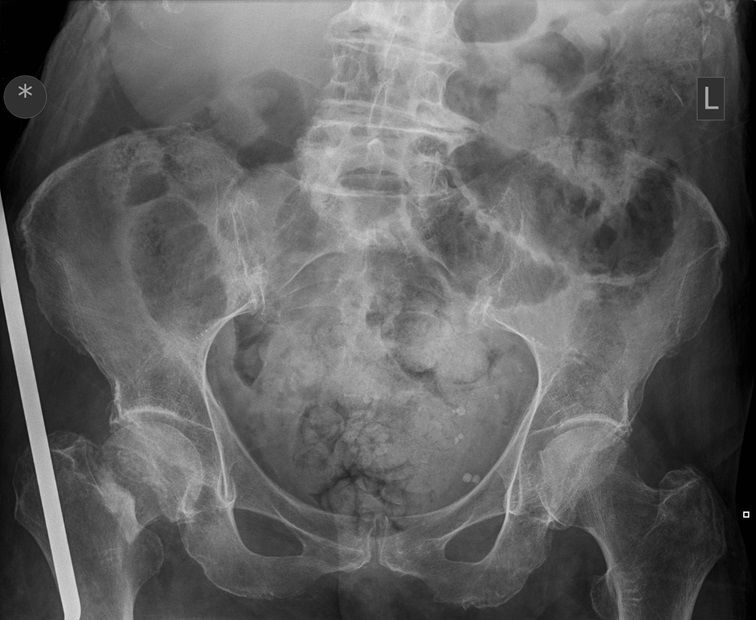

Question 2

Question

Which operation would you perform?

Answer

• THR

• Hemiarthroplasty